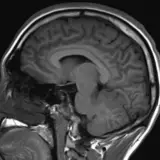

Over 2,100 interactive radiology cases, curated by radiologists for your level of training. Scroll, window, and view cases full screen — just like on PACS. Click linked findings in each writeup to jump straight to them on the image. Cases include sample reports, a focused discussion section, original illustrations, and videos.

Neuro Fellowship — a course tailored for fellows and practicing radiologists with in-depth reviews of advanced neuro topics like brain tumors, featuring rare diagnoses, differentials, and clinical pearls.

Casos totalmente interativos com as ferramentas que você espera em um PACS — rolagem, ajuste de janela, zoom, movimentação, medidas, ROIs e modo de tela cheia.

Anotações detalhadas destacam os achados principais diretamente nos casos. Clique nos achados vinculados nas descrições dos casos para ir ao local exato no exame.

Aprenda com eficiência com achados de imagem anotados e ilustrações